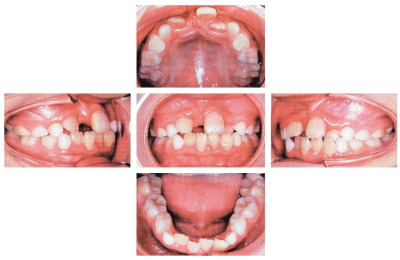

9歳の男児。審美不良を主訴として来院した。2か月前に外傷によって上顎右側中切歯が脱落し、傷は治ったが、そのままにした場合にどうなるか心配しているという。初診時の口腔内写真とエックス線画像を別に示す。

保護者への説明で適切なのはどれか。1つ選べ。